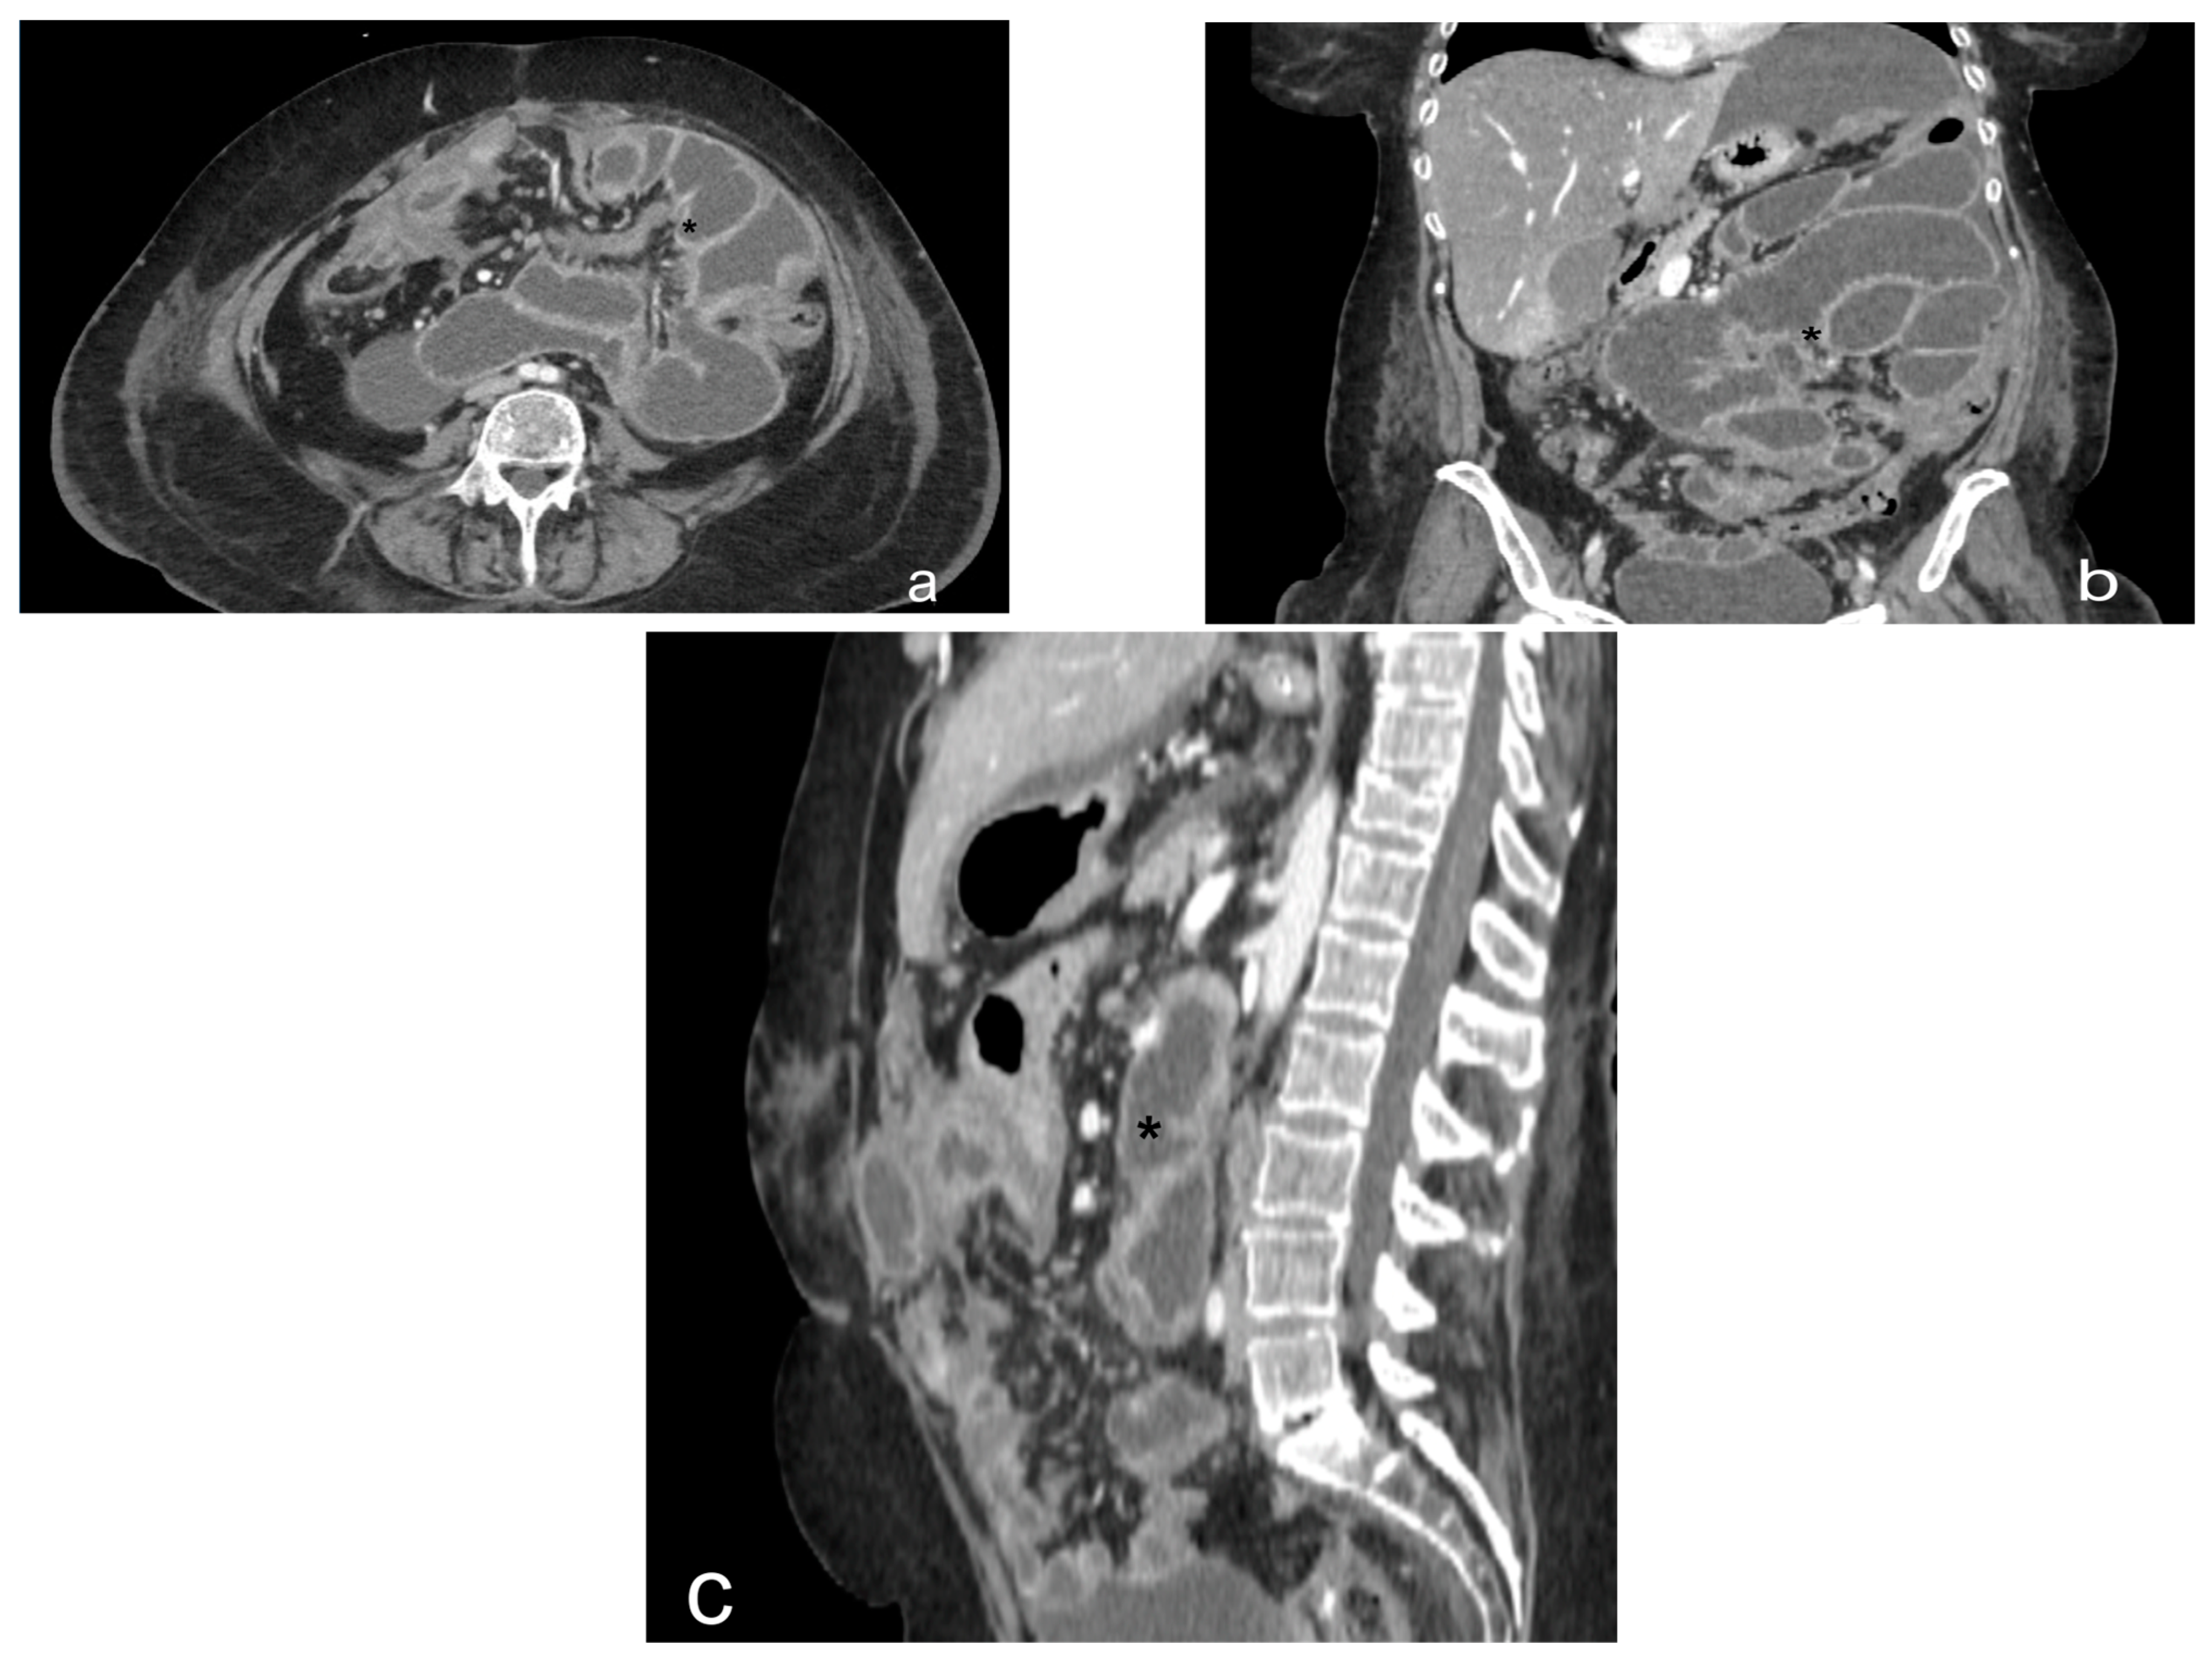

- Nodular pattern: characterized by the presence of nodular implants >5 mm in diameter (Figure 8).

- Theca pattern: characterized by a nodular thickening of the visceral peritoneum lining the loops of the small bowel. Sometimes, this heteroplasic thickening generates narrowing, with the consequent obstruction and dilation of the proximal loops, a condition also referred to as “frozen pelvis” [95] (Figure 12).